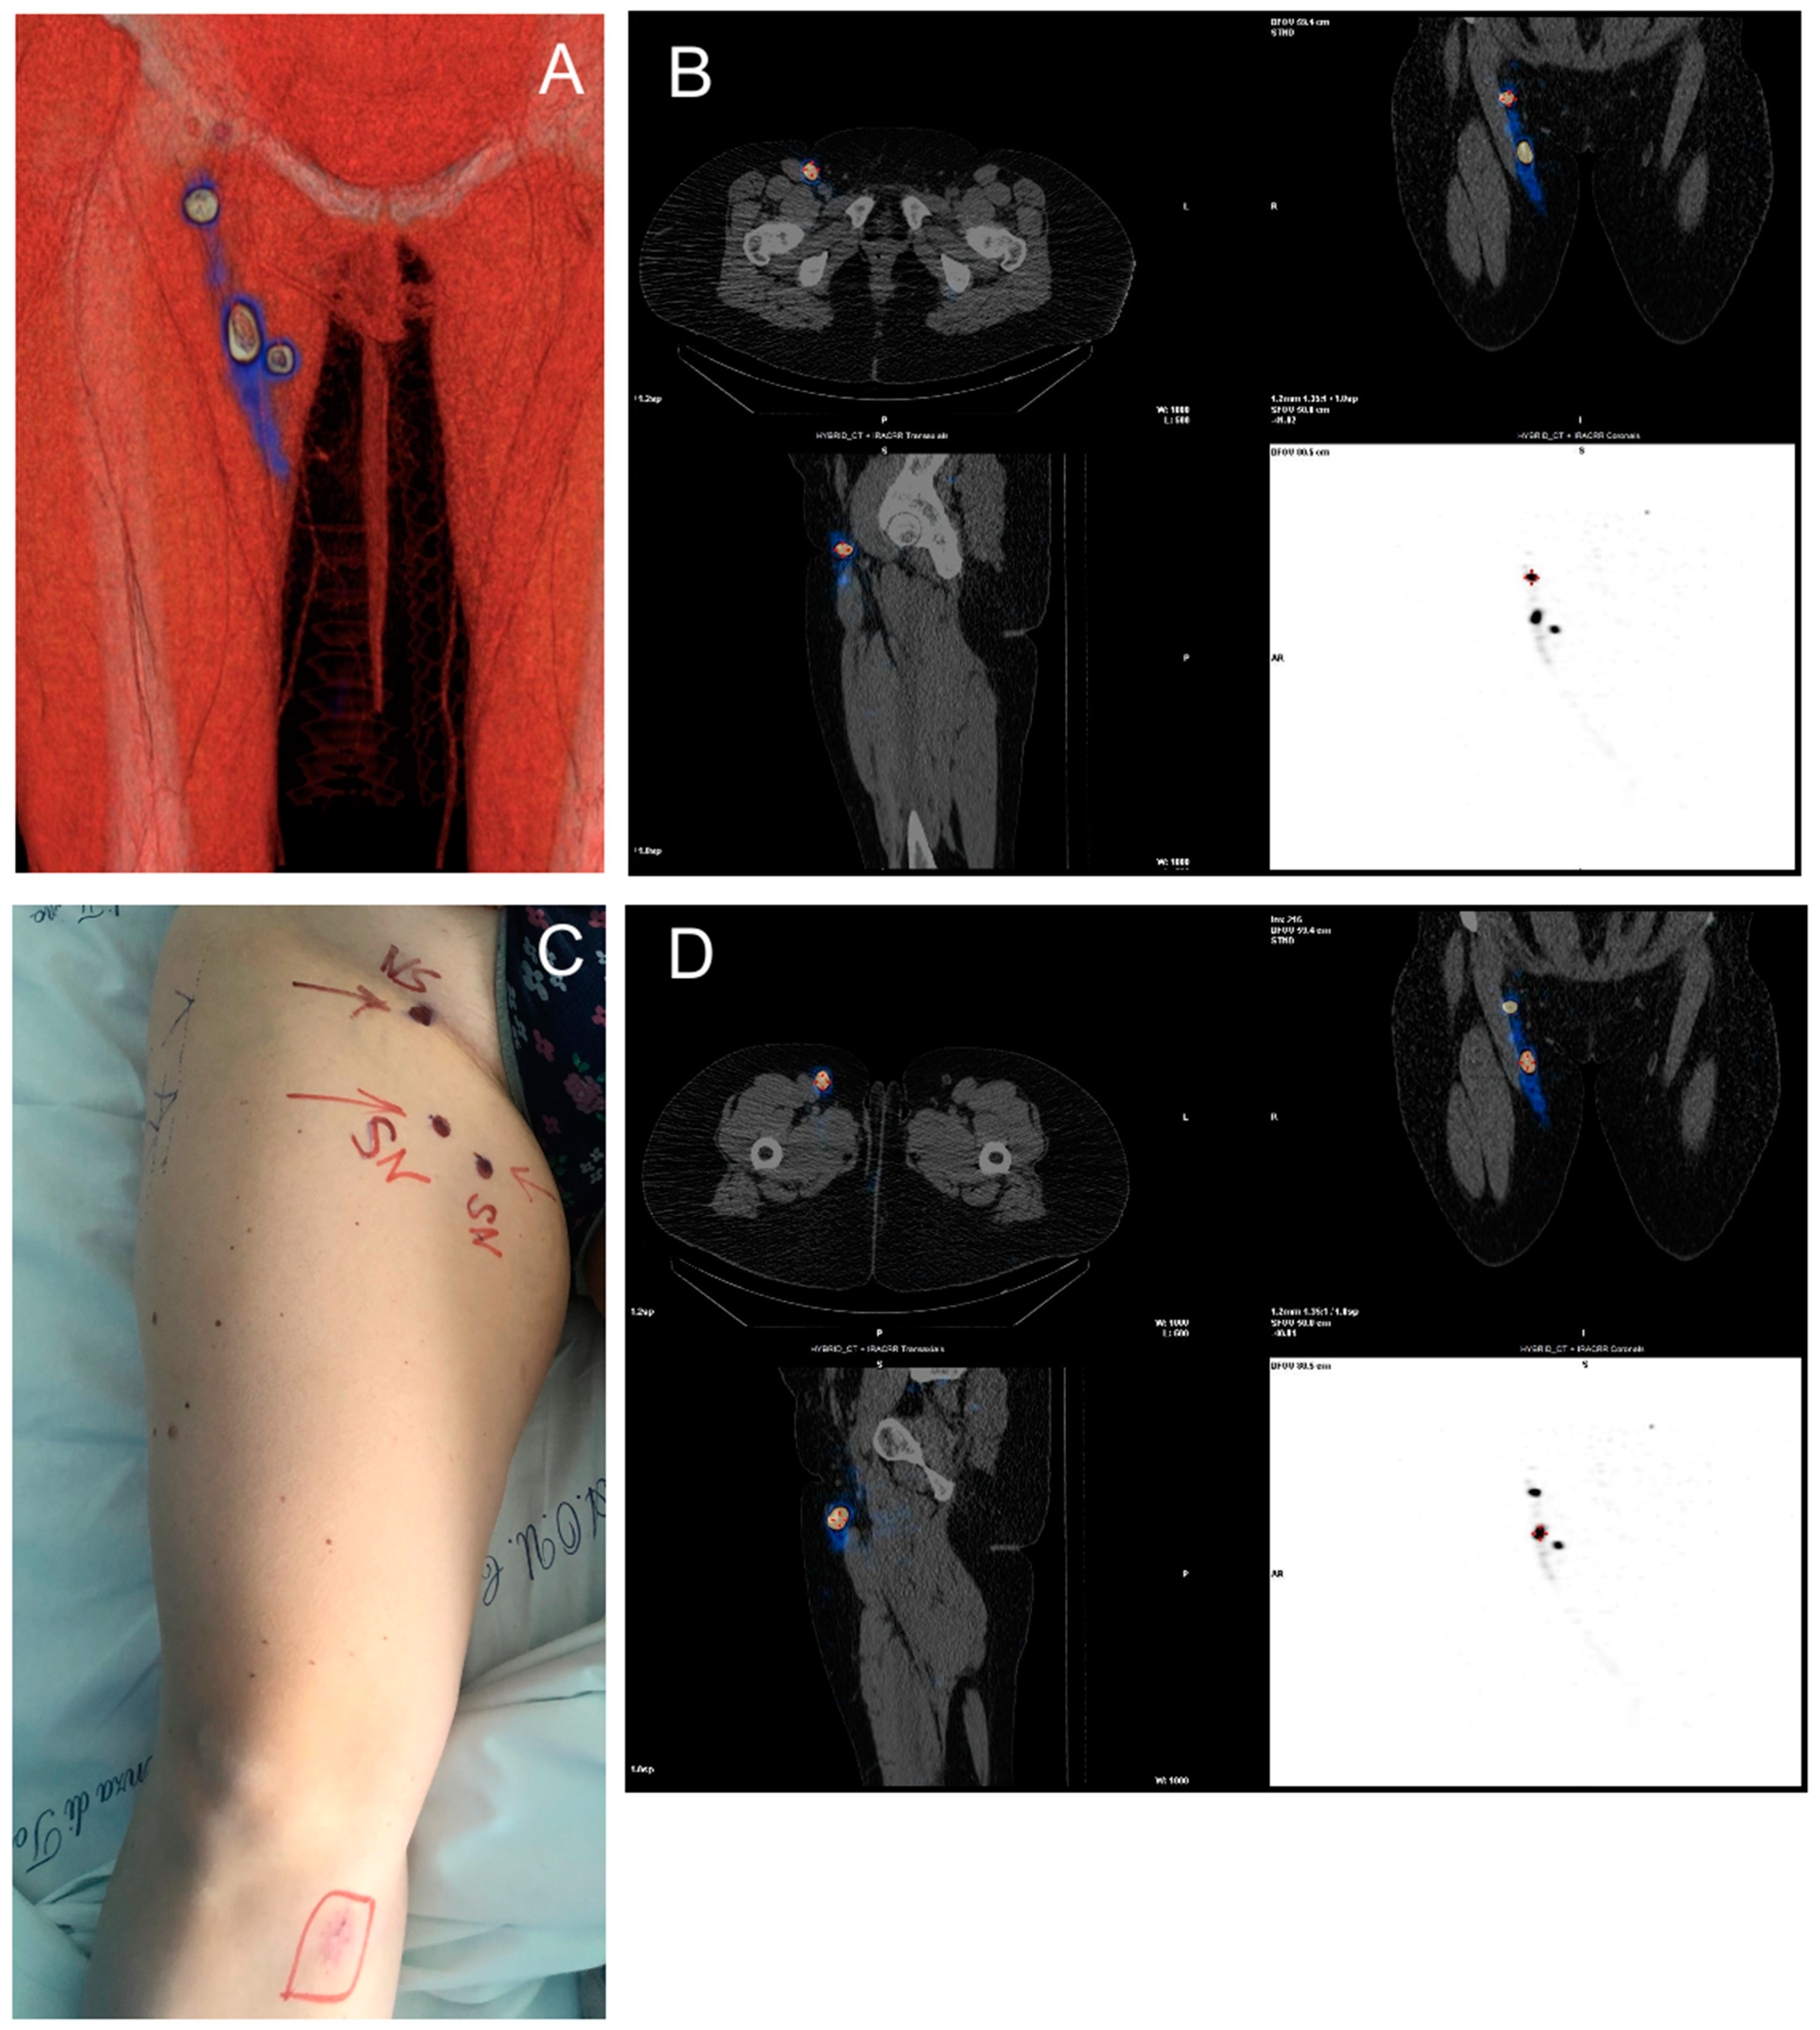

SPECT-CT Technique

3.2. SPECT-CT